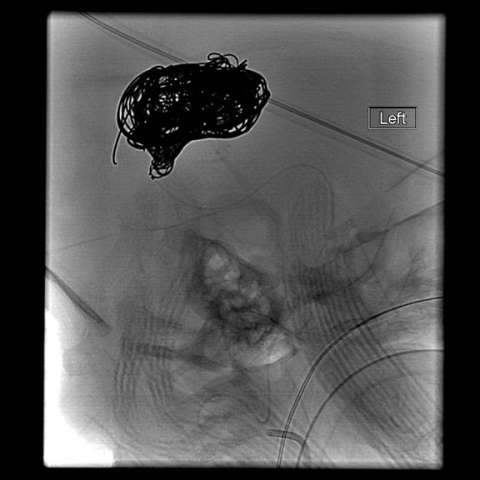

- Cranial Angiography - cranial angiography is usually performed in the setting of endovascular treatment

Endovascular embolization is the preferred method of treatment. In an embolization, the abnormal blood vessels are intentionally closed with soft platinum coils or liquid embolic agents, which reduce the abnormal blood flow to the vein of Galen. Sometimes, several procedures are required over a period of several months.